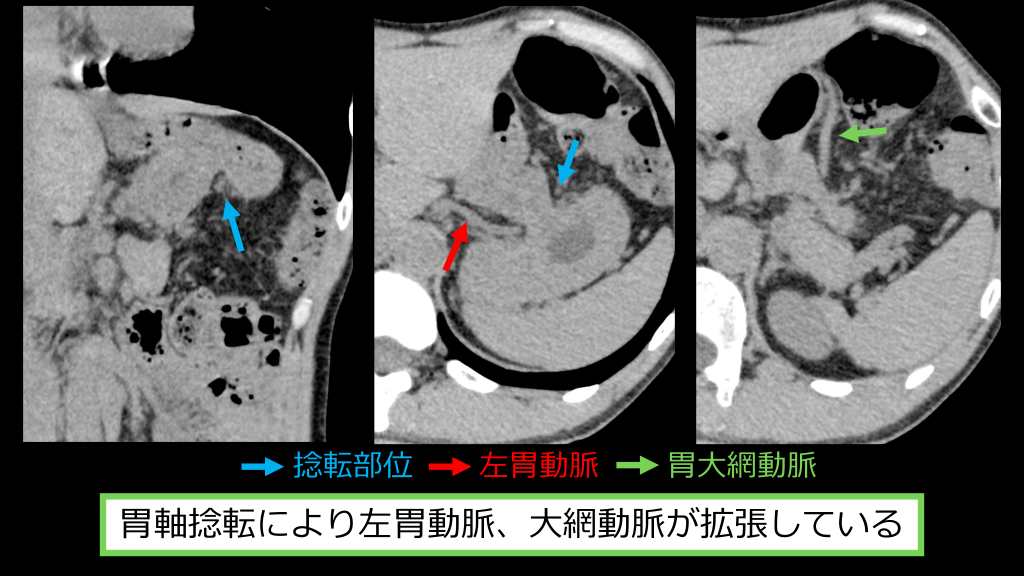

捻転部位 左胃動脈 胃⼤網動脈 胃軸捻転により左胃動脈、⼤網動脈が拡張している

胃軸捻転により左胃動脈、⼤網動脈が拡張している